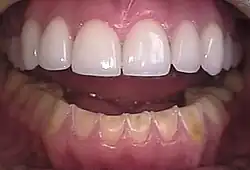

| Loss of enamel (acid erosion) from the inside of the upper front teeth as a result of bulimia | |

People with bulimia are at a higher risk to have an affective disorder, such as depression or general anxiety disorder. One study found 70% had depression at some time in their lives (as opposed to 26% for adult females in the general population), rising to 88% for all affective disorders combined.[24] Another study in the Journal of Affective Disorders found that of the population of patients that were diagnosed with an eating disorder according to the DSM-V guidelines about 27% also suffered from bipolar disorder. Within this article, the majority of the patients were diagnosed with bulimia nervosa, the second most common condition reported was binge-eating disorder.[25] Some individuals with anorexia nervosa exhibit episodes of bulimic tendencies through purging (either through self-induced vomiting or laxatives) as a way to quickly remove food in their system.[26] There may be an increased risk for diabetes mellitus type 2.[27] Bulimia also has negative effects on a person's teeth due to the acid passed through the mouth from frequent vomiting causing acid erosion, mainly on the posterior dental surface.